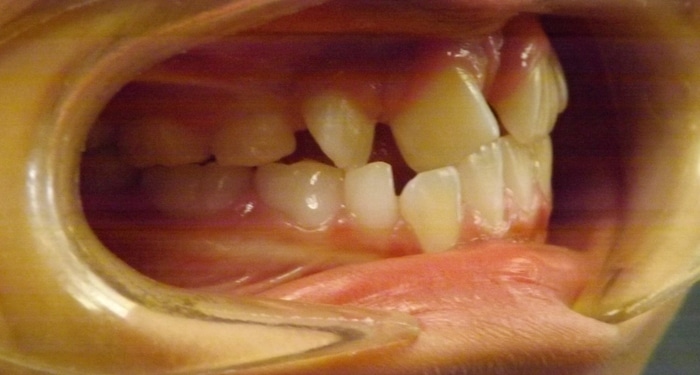

Christopher was a Phase I case that presented with a Class III bite on the right side and around a 90 degree rotation of his upper right central and lateral incisors. During Phase I we placed upper 2×4 brackets (brackets on upper 4 front permanent teeth) since he still had several primary teeth left. We began Phase II and at this time Christopher had 5 mm of upper crowding and 3 mm of lower crowding. We placed brackets on the upper and lower arches and had him wear elastics during treatment. Christopher ended with a really beautiful Class I bite and smile.